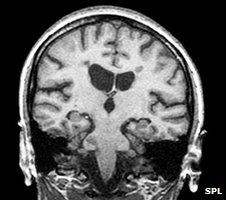

He says having more MRI scanners, a machine which takes a detailed picture of the brain, would help.

"They would certainly help in the diagnoses of multiple sclerosis because they would spot inflammation of the brain."

MRI scan of a coronal section through a brain in multiple sclerosis